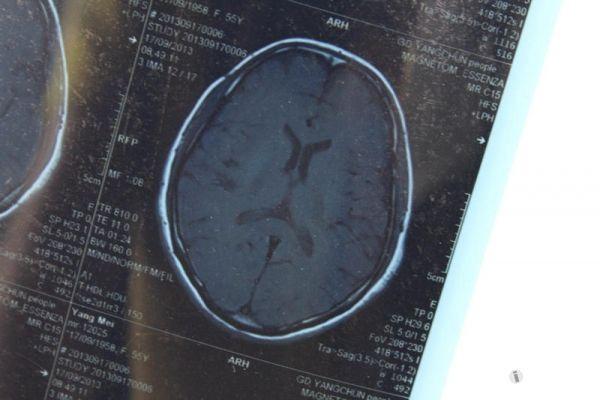

脑部占位病变CT,MRI图片,请帮忙诊断

最近感图样,无其它脑病病史

考虑脑膜瘤!!

磁共振没有平扫,增强矢状位没找到病灶。像脑膜瘤。

图片不是很清楚,应该是脑膜瘤!